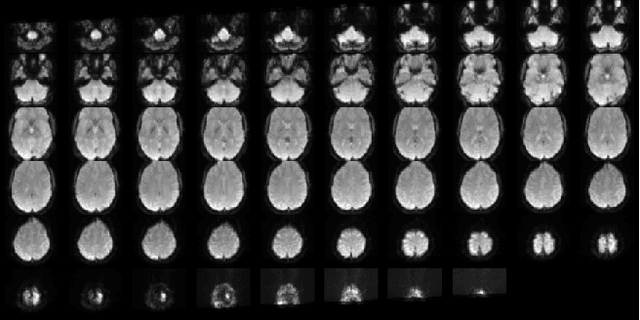

Abstract:In spite of years of research, the mechanisms that underlie the development of schizophrenia, as well as its relapse, symptomatology, and treatment, continue to be a mystery. The absence of appropriate analytic tools to deal with the variable and complicated nature of schizophrenia may be one of the factors that contribute to the development of this disorder. Deep learning is a subfield of artificial intelligence that was inspired by the nervous system. In recent years, deep learning has made it easier to model and analyse complicated, high-dimensional, and nonlinear systems. Research on schizophrenia is one of the many areas of study that has been revolutionised as a result of the outstanding accuracy that deep learning algorithms have demonstrated in classification and prediction tasks. Deep learning has the potential to become a powerful tool for understanding the mechanisms that are at the root of schizophrenia. In addition, a growing variety of techniques aimed at improving model interpretability and causal reasoning are contributing to this trend. Using multi-site fMRI data and a variety of deep learning approaches, this study seeks to identify different types of schizophrenia. Our proposed method of temporal aggregation of the 4D fMRI data outperforms existing work. In addition, this study aims to shed light on the strength of connections between various brain areas in schizophrenia individuals.